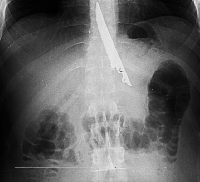

Любого доктора можно быстро подготовить как рентгенлаборанта и дать необходимые знания для оценки рентгенограмм.

Изучение проблемы низкого качества рентгенограмм на Вашем оборудовании.

Мобильный рентгенаппарат + оцифровщик. Получение рентгеновского изображения на экране ноутбука. Вариант за 1,4 миллиона рублей под ключ.

Мобильный рентгенаппарат с печатью рентгенограмм на рентгеновской пленке. Цена 700000 рублей.